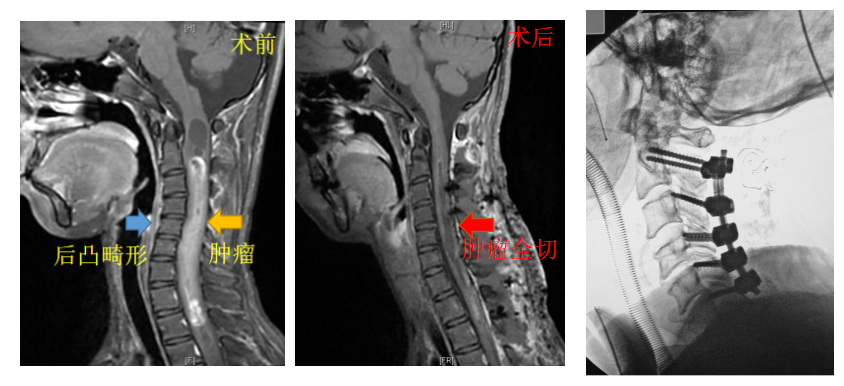

此次就诊,明明还被查出颈椎后凸畸形,希望能够同期手术处理。这样一来,手术就需要采用俯卧位,切除脊髓肿瘤的同时一期矫正后凸畸形,手术最大风险是术后呼吸障碍、心率血压不稳和四肢瘫痪,在技术上具有极大的挑战性。

经全面研究,王贵怀制订了“脊髓肿瘤切除+后凸畸形矫正”联合术,手术由王贵怀主刀,神经外科主治医师孙振兴辅助。术中首先由孙振兴使用超声骨刀,铣下颈椎第2节到胸椎第2节,后切开并悬吊硬脊膜,王贵怀在神经电生理监测下,谨慎辨别脊髓后正中沟,小心切开脊髓,显露肿瘤。显微镜下,王贵怀交替使用显微双极、显微剪刀与显微吸引器,仔细分离脊髓与肿瘤的边界,在避免对周围神经组织造成损伤的情况下,慢慢剥离肿瘤直至完整全切除肿瘤。

术前(左)术后(中、右)对比影像

王贵怀把肿瘤切除、椎板复位后,指导孙振兴继续松解并截去部分颈椎侧块关节,小心植入颈椎螺钉进行固定,并对颈椎后凸进行矫正,术中O-ARM透视显示螺钉位置与后凸畸形矫正良好。历时8小时,手术顺利结束。由于术中对脊髓和神经组织保护较好,术中神经电生理监测波幅未有明显下降,麻醉没有出现心率、血压下降等情况,明明在ICU一天后转回了普通病房。